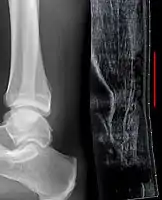

Achilles tendon avulsion seen on plain X-ray

Achilles tendon rupture

Transverse plane/Achilles tendon rupture

Achilles tendon rupture seen on ultrasound. Note discontinuity over several centimeters (red line). No fracture or avulsion (radiograph).